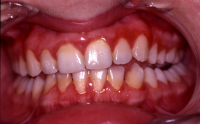

Gingival hälsa på intakt och reducerat parodontium.

Parodontal stabilitet karakteriseras av framgångsrik behandling genom kontroll av lokala och systemiska riskfaktorer, vilket resulterat i

- minimal blödning vid sondering (BVS < 10 % av tandytorna)

- fickdjup < 3 mm

- ingen progressiv parodontal nedbrytning/vävnadsförlust

- optimal förbättring i övriga kliniska parametrar hos behandlad parodontitpatient.